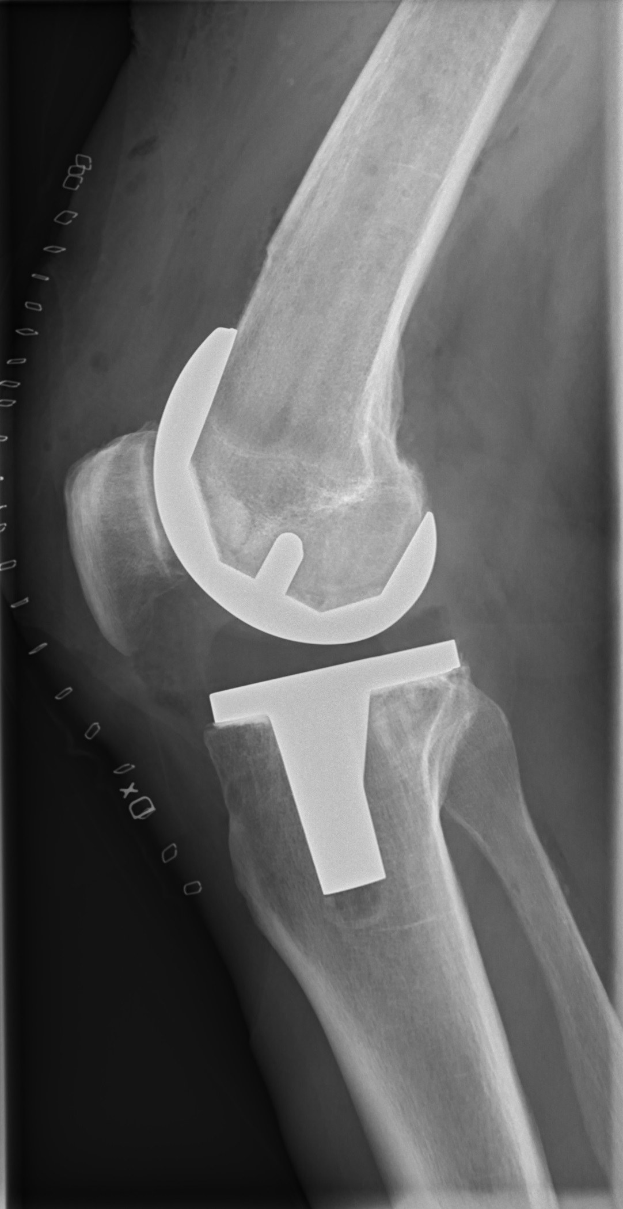

Mittelfeldspieler Robin Hack, der im Eröffnungsspiel des DFB-Pokals zweimal traf, fällt nach einer Operation am gerissenen Meniskus im rechten Knie mehrere Wochen aus. Sein Ausfall zwingt die Mannschaft zu personellen Anpassungen.